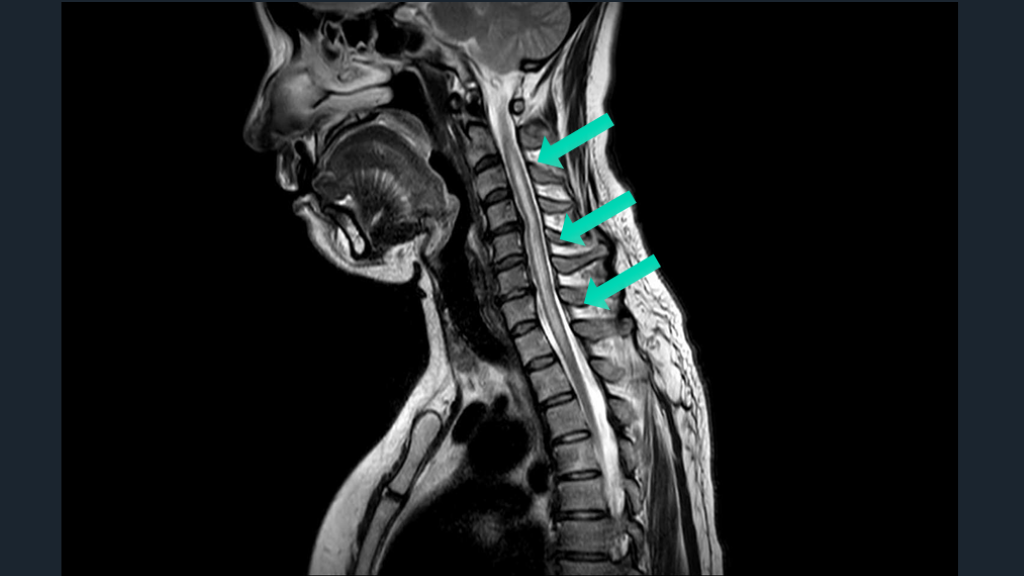

脊髄障害は、 悩むならwhole spine MRI 矢状断をとっておく。 TIPS

#53.

CASE 70歳女性例。突発発症の下肢対麻痺である。 先ほどのアイデアのごとく、4つの鑑別をまずは挙げる。 そして、MRIではどこを撮るのか?は正直、難しい。 正直、かっこつけずに、whole spine MRIでよいと思う。

#57.

脊髄障害の初手はwhole spineでよい。 脊髄緊急疾患でのWhole spine-MRIは推奨。 ER脊髄障害S/Oで、約半数の症例の脊髄緊急疾患診断に有用だった。 特に、外傷、麻痺、および排便/排尿症状患者で価値ある可能性 解説 Curr Probl Diagn Radiol. 2021;50:637-645. Handb Clin Neurol. 2017:140:319-335.

#58.

脊髄障害の初手はwhole spineでよい。 脊髄障害の高位診断は正直難しい。 症状の高位と実際の脊髄障害の高位は異なる。 実際の障害高位は、症状の高位よりも、より上にある。 対麻痺なら、腰髄レベルよりもより高位でどこでもあり。 腰髄レベルMRIのみ施行なら空振りリスクある。 それなら、WS-MRIの撮影でもよかろう。 解説

#59.